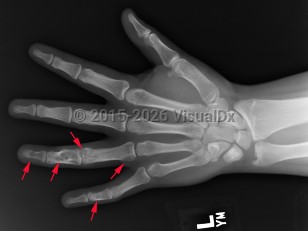

Causes / typical injury mechanism: Enchondroma is a benign, hyaline-cartilage producing tumor located in the medullary canal of the diaphysis or metaphysis of long bones.

Classic history and presentation: The proximal phalanx is the typical location. These tumors are also common incidental findings in the distal femur, proximal humerus, and tibia. Mean length is usually less than 5 cm.

Prevalence: Enchondroma is a latent lesion that comprises 15%-25% of cartilage tumors. It is the most common hand tumor, accounting for 90% of cases. Enchondroma usually presents in the third and fourth decades of life and occurs equally between both sexes.

Pathophysiology: Enchondroma pathophysiology is believed to involve incomplete endochondral ossification in which physeal remnants become entrapped in the medullary cavity of the metaphysis and proliferate. In the hand, enchondromas are typically diagnosed after a pathologic fracture. Elsewhere, they are typically an asymptomatic incidental finding on x-ray or advanced imaging performed for other reasons. Pain is usually due to a nearby abnormality rather than the tumor itself.